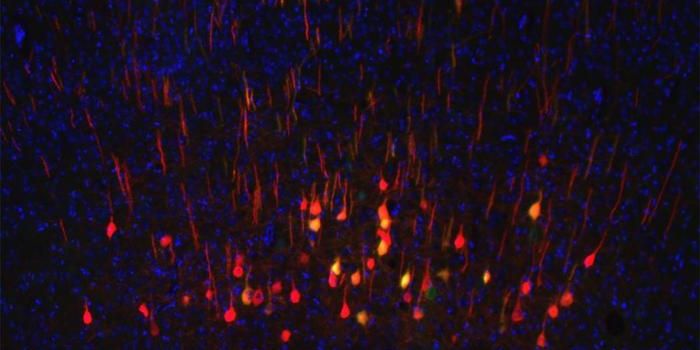

OCT 17, 2023Clinical & Molecular DXIn this photo, courtesy UC San Diego Health Sciences, regenerating neurons (yellow) can be seen along with non-regenerat ...